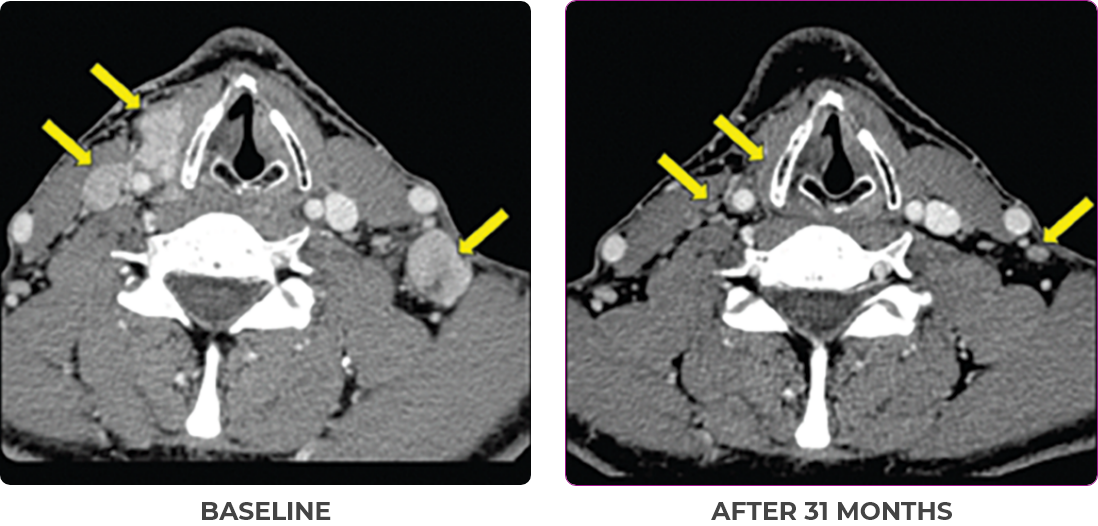

PATIENT CASE:

METASTATIC, RAIa-REFRACTORY,

PAPILLARY THYROID CANCER1

- 56-year-old female with PTCa that had metastasized to multiple sites, including the brain

- Progression after first- and second-line systemic treatment

- PRa after 4 weeks on VITRAKVI® (larotrectinib); CRa after 8 weeks

- At last assessment, complete response was sustained over an 11-month period

Clinical presentation1

- Patient was assessed to have metastatic, rapidly progressive, RAl-refractory PTC based on imaging that revealed multiple metastatic sites, including the neck, mediastinum, lung, scalp, and bones

- Biopsy of a scalp lesion helped to confirm the PTC metastasis

- Metastases to the brain and liver were observed after progression on systemic treatments

VITRAKVI treatment1

- VITRAKVI 100 mg twice daily orally

Response to VITRAKVI1

- After 8 weeks on VITRAKVI, all target lesions had disappeared, demonstrating a complete response

- The complete response was sustained over 11 months of treatment with VITRAKVI

- Patient experienced Grade 1 fatigue and mild hepatic enzyme elevation

Response in primary and metastatic lesions1

MRIa imagery of the lungs. Arrow indicates large target lesion in left lung.1

SCAN 1: LUNG

MRIa imagery of the brain. Arrow indicates large target lesion in left lung.1

aMRI, magnetic resonance imaging.

Images courtesy of Dr Fabian Pitoia.

aCR, complete response; MRI, magnetic resonance imaging; PR, partial response; PTC, papillary thyroid cancer; RAI, radioactive iodine.